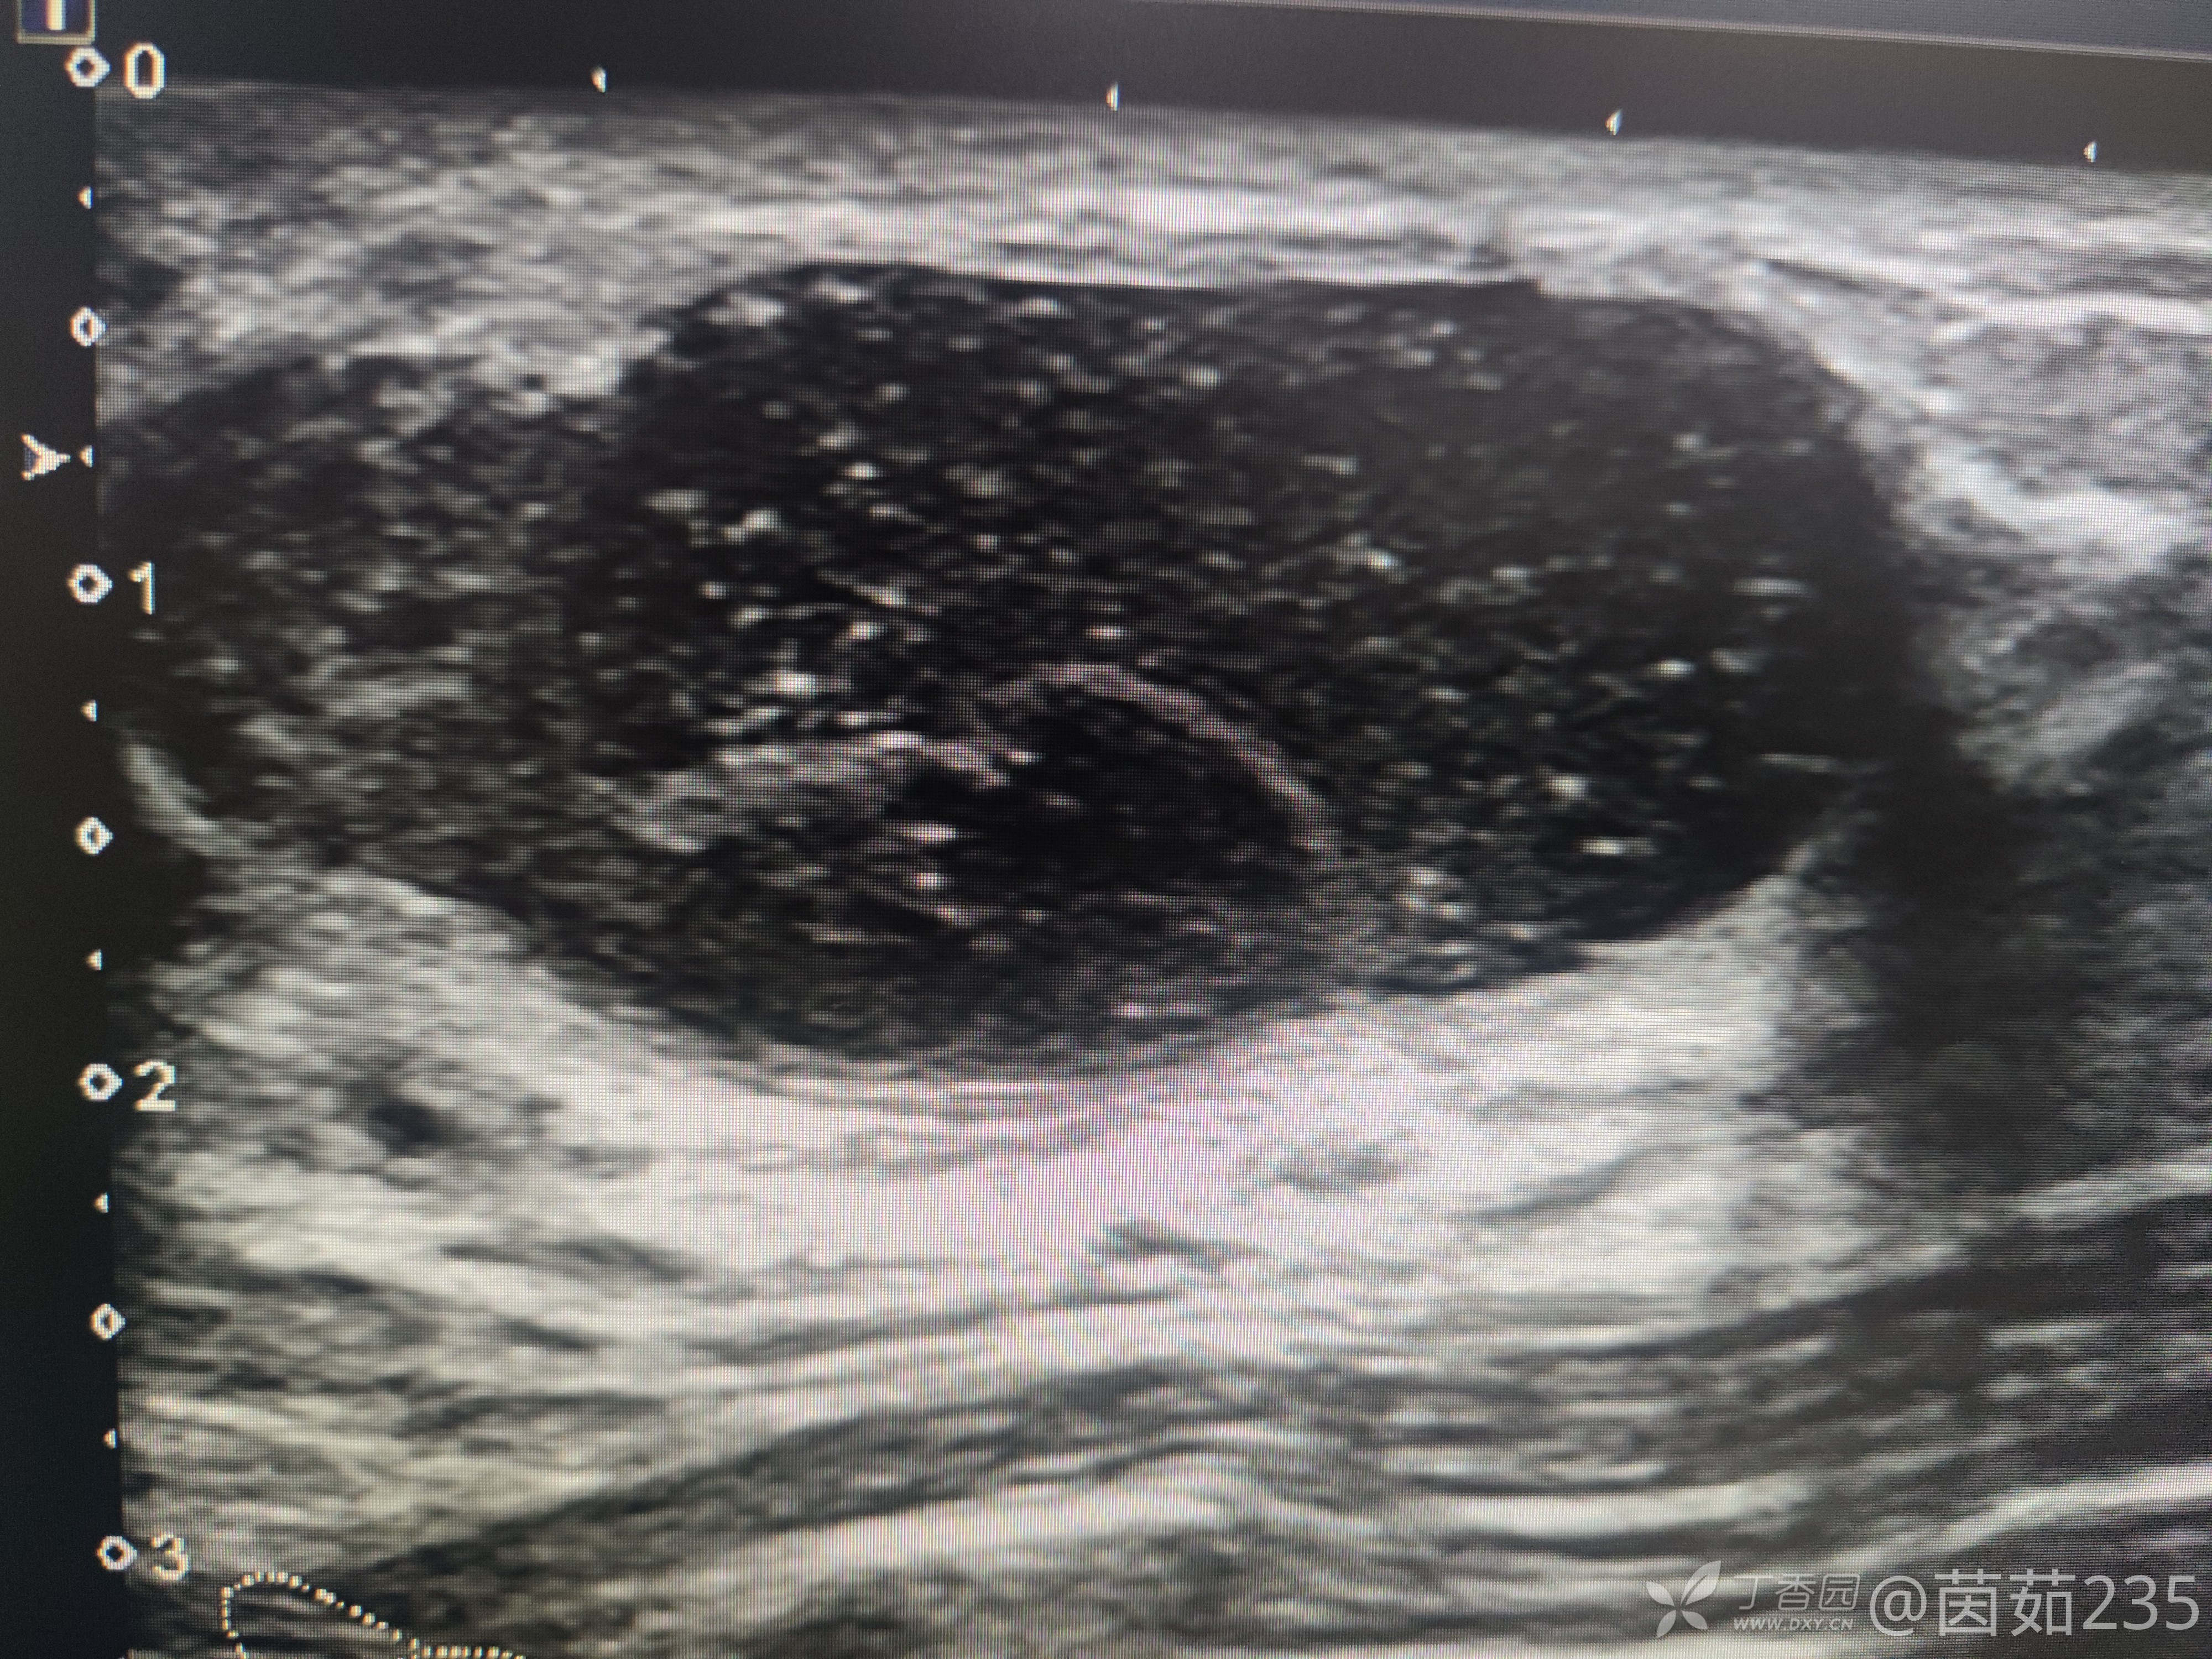

右侧乳腺12点乳晕后方腺体内可见一低回声包块,大小37✖️16mm,边界清,壁厚,内回声不均,可见数个彗星尾。来看看图,你们觉得该分几类?考虑是什么?